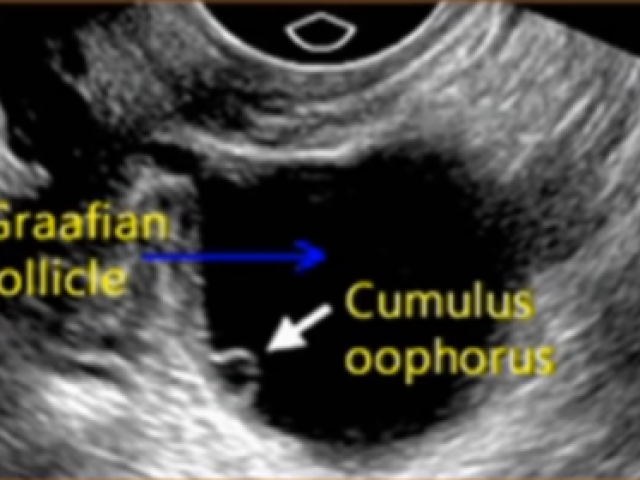

Comprehensive Ob/Gyn Ultrasound Education Modules

Gynecology Ultrasound Topics (6 CMES) $13.49 Click Here

Normal System Anatomy and Associated Abnormalities (9 CMES) $13.49 Click Here